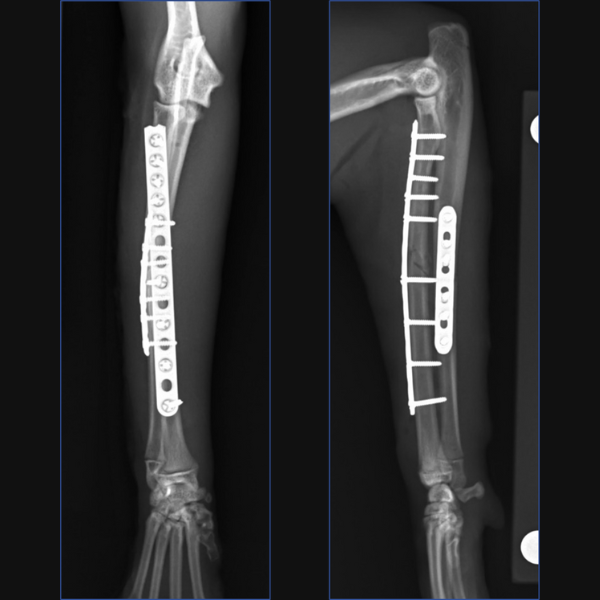

For Bundle we performed open reduction and internal fixation using a 14-hole 1.5/2.0 Veterinary Cuttable Plate (VCP) on the radius and a 6-hole 1.5mm Locking Compression Plate (LCP) on the ulna. This was all performed through single craniolateral approach. I think we have addressed one reason why we chose dual bone fixation in this case, due to the lower complication rate that could be anticipated with that. Another reason is that in people at least, insufficient stabilization has been associated with an increased risk of synostosis formation so rigid, dual-bone fixation was desired here to limit that. But why choose a lateral plate on the ulna rather than an IM pin?

You could debate the choice of a single approach for fixation here based on some literature in the human field. I have generally preferred a single approach with the suture line not lying directly over either of my implants but that is simple personal preference. While it is based on a very specific posterior approach to the radius and ulna called the Boyd approach, and may not be transferrable to our feline patients, there is some evidence in humans with radius-ulna fractures that placement of dual bone fixation through a single approach is associated with a higher risk of synostosis formation than placement of implants through two separate approaches. Postulated reasons include extensive soft-tissue exposure, increased risk of development of radioulnar hematoma or interosseous damage and potential malpositioning of one of the implants due to suboptimal exposure of both bones. Further research is required to determine whether single or dual approaches may be associated with different complication rates in cats, but certainly, you could argue that the radial plate is positioned slightly too laterally at the proximal extent here and that a single approach may have contributed to that.

In terms of critiquing my postoperative radiographs here from Figure 3, in addition to the radial plate being slightly too lateral at the proximal extent, the first screw distal to the fracture is close to caudodistal extent of the short oblique fracture line. This may have rendered this screw monocortical and additionally, may have caused some fragmentation of the fracture line at this point, so not ideal, but we do have an additional three bicortical screws distally on the radius in addition to three screws in the ulna so I did not consider that this warranted any immediate revision surgery.